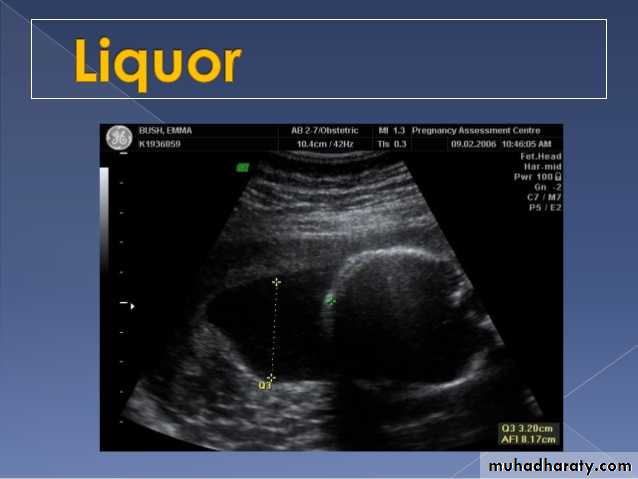

Poly hydraminous :

Poly hydraminos refers to a situation where the amniotic fluid volume is more than expected for gestational age.

It is generally defined as:

amniotic fluid index (AFI) > 25 cm

largest fluid pocket depth (maximal vertical pocket (MVP)) greater than 8 cm

overall amniotic fluid volume larger than 1500-2000 cc3